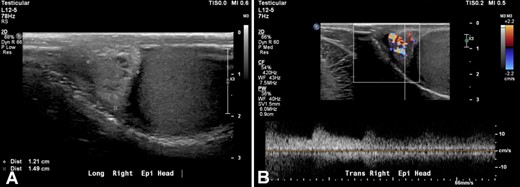

Two months later, the patient continued to have mild urgency during the day and nocturia with not much improvement in his symptoms. He also complained of right back pain that radiated to the right testicle. Sitting down and laying down made it better, while standing made it worse. The pain was more prominent in the morning. The patient denied trauma to the genital area. He also started feeling a “liquid filled sac” on the right testicle. Testicular sonogram was performed revealing a 1.2 cm hypoechoic, hypervascular mass in the right epididymal head (Figure 2).

PCE is a benign tumor and the second most common neoplasm of the epididymis.1 It develops within the efferent ductules of the head of the epididymis as a solid, cystic, or partially cystic mass usually measuring up to 3 cm in diameter and is usually asymptomatic.2,39 This benign neoplasm can present in a unilateral or bilateral fashion, wherein bilateral lesions are more associated with von Hippel Lindau Disease (VHLD). It mostly affects young men, mean age 35 years, but has been reported between in patients as young as 16 and as old as 76 years of age.1 The modality of choice for evaluating paratesticular/epididymal masses is high-frequency ultrasonography and color flow doppler.40 Computed tomography (CT) is used for staging once a diagnosis of malignant neoplasia is made.41